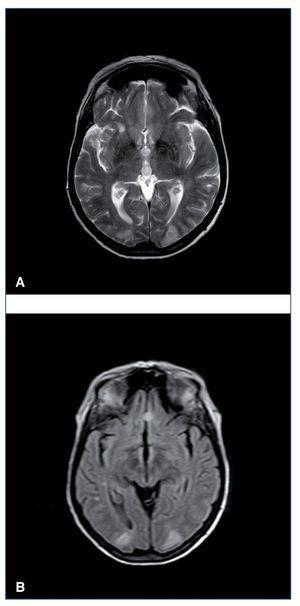

RM cerebral (secuencias T2 y DW): áreas bilaterales de señal hiperintensa, corticosubcorticales, afectando ambos lóbulos occipitales y parietales.

Figura 1. Resonancia magnética cerebral en secuencias T2 (A) y FLAIR (B). Imágenes hiperintensas en la región corticosubcortical de ambos lóbulos occipitales.

Cuando se sospecha encefalopatía (deterioro cognitivo, crisis convulsivas, estupor, coma) es fundamental la realización de una prueba de imagen cerebral, TC o RM para descartar una leucoencefalopatía posterior reversible. Aunque en la TC se pueden ver imágenes hipodensas en los sectores afectados por el edema y serviría para el diagnóstico, la RM es la técnica de elección (secuencias T2 y FLAIR, que mostrarían señales hiperintensas en la sustancia blanca subcortical a nivel parietooccipital). En contexto infeccioso deberá realizarse punción lumbar con estudio microbiológico del líquido cefalorraquídeo.